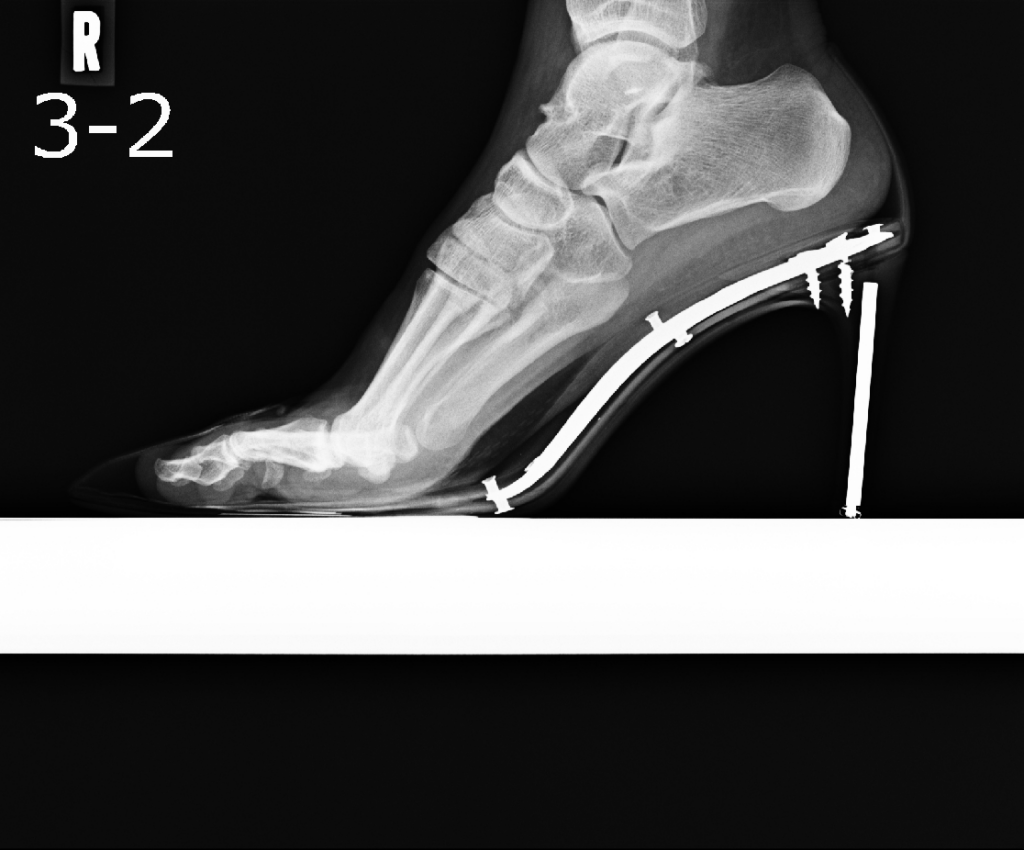

ヒールを履いていると踵が上がり、体重が前方向に偏ります。またヒールを履くと角度がつくため中足骨が縦向きに地面に着くようになり、中足骨の骨頭部に圧力が集中します。